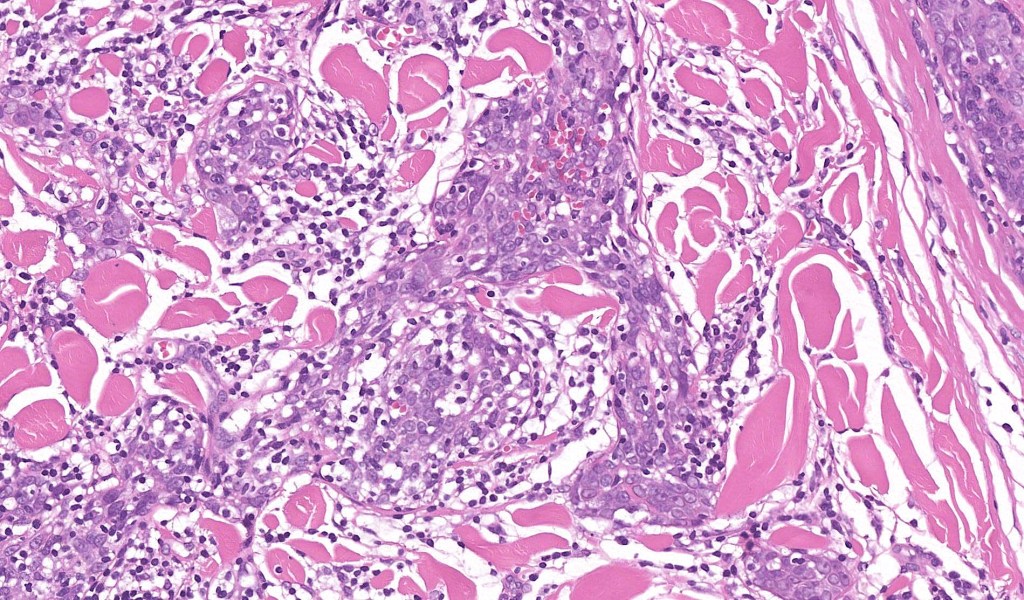

•Dermal generally circumscribed tumor nodule (less often it may show an infiltrative border)

•Syncytial epithelial component in nests, cords or sheets surrounded by an intense lymphoplasmacytic infiltrate

•Epithelial cells are large with abundant cytoplasm and vesicular nuclei with conspicuous nucleoli

•Marked mitotic activity, variable pleomorphism

•Absence of an epidermal connection